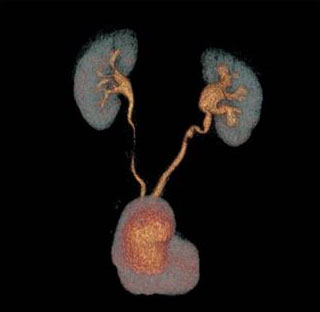

Figure 4: Two months CTU reconstruction of urinary system.

A follow-up computed tomography urography (CTU) was performed two months after the surgery, confirming the absence of urinary fistula and the good vascularization of the appendix (Figure 3 and Figure 4).